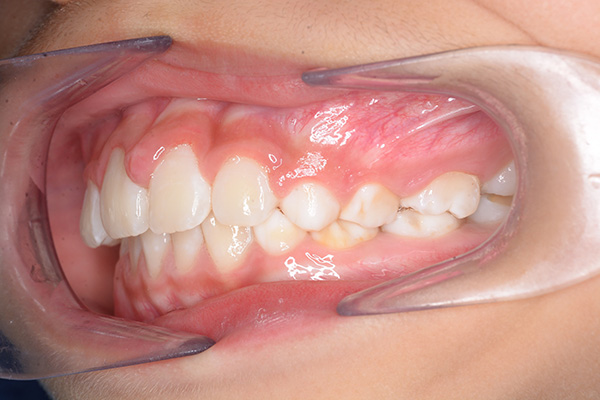

| 主訴 | 上顎前歯のでこぼこ | 診断名 | アングルⅡ級叢生症例 | ||||

|---|---|---|---|---|---|---|---|

| 初診時年齢 | 6歳9ヵ月 | 性別 | 男 | 動的治療期間 | 6ヵ月 | ||

| 既往歴として上顎正中過剰歯(2本)は抜去済み。その影響で上顎右側中切歯は捻転して萌出しており、下顎右側中切歯と早期接触が認められたため2x4(上顎のみブラケット装着)にて前歯部の改善を行った。現在は永久歯列完成まで経過観察を行い、希望があれば口元の突出感を改善するために本格矯正治療を行うことにしている。 | |

| セファロ所見 | 上下顎骨は調和のとれた位置関係を示していたが、頭蓋に対して両顎共に前方に位置していた。上下顎前歯は唇側傾斜していた。 |

| パノラマ所見 | 過剰歯抜歯後は特に問題ない。 |

| 批評・予后 | 早期治療によって前歯部の咬合干渉は回避され、その後の永久歯への交換は順調である。 |